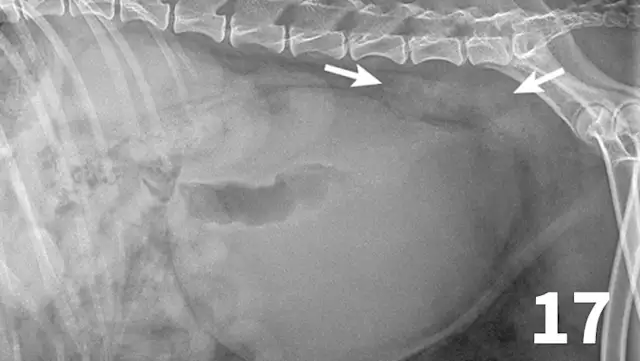

Survey radiographs of the urinary bladder are helpful for evaluation of size and location and for detection of radiopaque calculi. Urinary bladder distention is readily detected (Figure 17). Radiographs are of limited value in evaluating mural disease because the bladder wall cannot be differentiated from the fluid contained within the bladder. Bladder wall thickening (eg, bacterial inflammation, polypoid cystitis, neoplasia) is best evaluated by ultrasonography or double-contrast cystography (Figure 18). It should be noted that the degree of bladder filling can affect bladder wall thickness. For example, a small, mildly distended bladder may appear to have a thickened bladder wall on ultrasound compared with a moderately or severely distended bladder (Figure 19). This potential disadvantage can often be overcome by reevaluating the bladder several hours after preventing voiding.

This dog had a severely distended urinary bladder on evaluation of lateral abdominal radiographs. Ill-defined, soft tissue opacity was present in the region of the medial iliac lymph nodes (arrows). The dog had urethral neoplasia, which was the cause of the urinary outflow obstruction and lymph node enlargement.